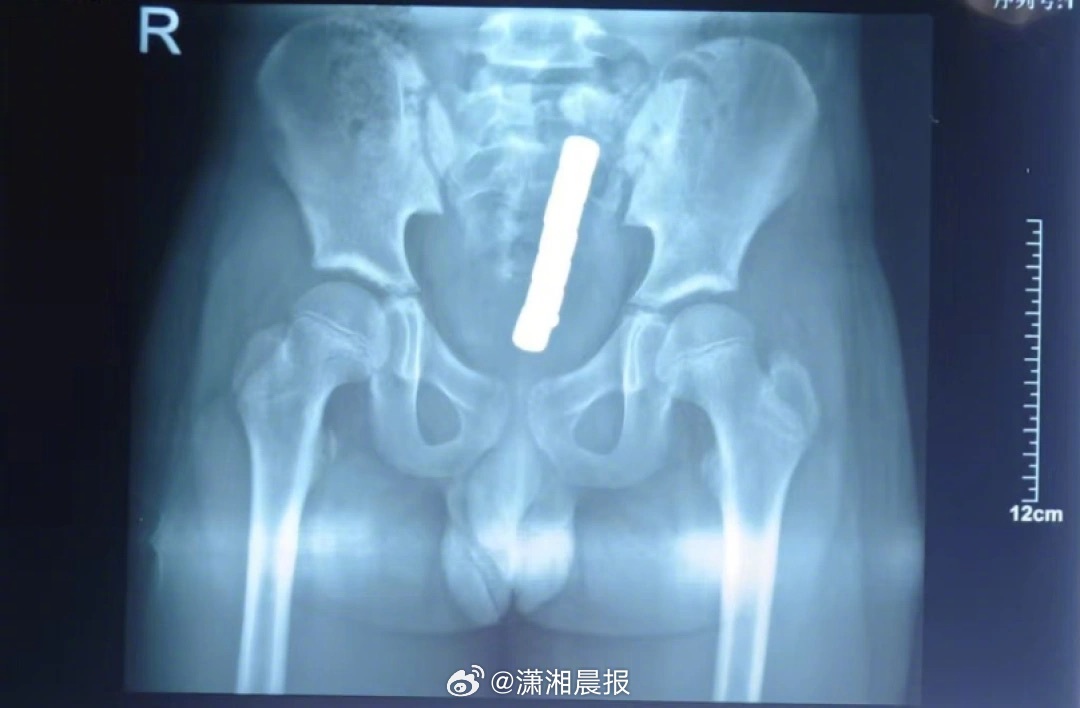

起初,家长并未察觉异常,直到小颖出现持续腹痛、腹胀等不适,使用开塞露通便后仅排出5颗磁力珠,剩余3颗滞留体内。家人紧急送医,经检查确诊为直肠穿孔,情况十分危急。

该院小儿普外科主任王国彦介绍,多颗磁力珠进入直肠后,会因磁力相互吸附,持续夹紧肠壁,造成局部组织缺血、坏死,最终引发肠道穿孔。手术中,医生发现小颖肠道存在多处穿孔,随即为其实施直肠修补术+乙状结肠造口术+内镜下直肠内异物去除术。经过医护团队精心护理,小颖腹腔感染得到有效控制,肠道功能逐步恢复,但仍需在三个月后接受造口回纳手术。

医生提醒,儿童误吞或误塞磁力珠,切勿自行处理。无论是否出现不适症状,一旦发现需立即送医,通过X光、CT等检查明确异物位置与数量,评估肠道损伤程度。未造成严重损伤时,可通过内镜微创取出;若已出现穿孔、梗阻,则必须紧急手术干预。